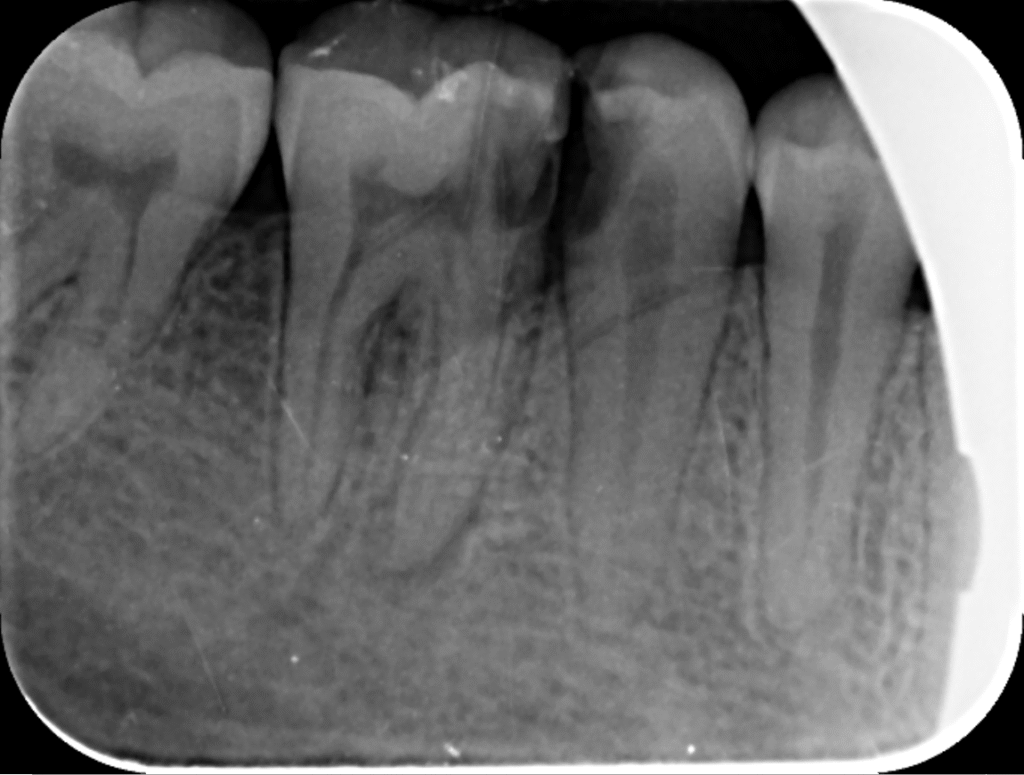

در ابتدا، دندانپزشک یک معاینه کامل انجام می‌دهد و با استفاده از تصاویر اشعه ایکس، وضعیت دندان را بررسی می‌کند. این مرحله برای تعیین نیاز به درمان مجدد و برنامه‌ریزی مراحل بعدی حیاتی است. در این جلسه، دندانپزشک ممکن است سوالاتی درباره تاریخچه پزشکی و دندانی بیمار بپرسد.

بررسی مجدد وضعیت دندان

پس از پاکسازی، دندانپزشک دوباره وضعیت دندان را بررسی می‌کند تا اطمینان حاصل کند که تمام عفونت‌ها و باکتری‌ها از بین رفته‌اند. در این مرحله ممکن است دوباره تصاویر اشعه ایکس گرفته شود.